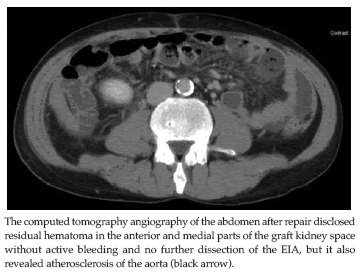

The following Doppler sonography of the graft kidney disclosed adequate perfusion without focal defect, and the serum creatinine concentration was 91.5 µmol/L 1 week after RTx. The pathology of the torn intima of the EIA showed only a mild intimal tear with mild atherosclerosis (Figure 2). The following computed tomography angiography of the abdomen after repair disclosed residual hematoma in anterior and medial parts of the graft kidney space without active bleeding, and no further dissection of the EIA (Figure 3), but it also revealed atherosclerosis of the aorta. For anticoagulation, heparinization with low molecular weight heparin was given for 3 days. Lifelong clopidogrel also was prescribed.The patient was discharged with a serum creatinine concentration level of 99.1 µmol/L without claudication 14 days postoperatively.

Figure 3. Computed Tomography Angiography of the Abdomen